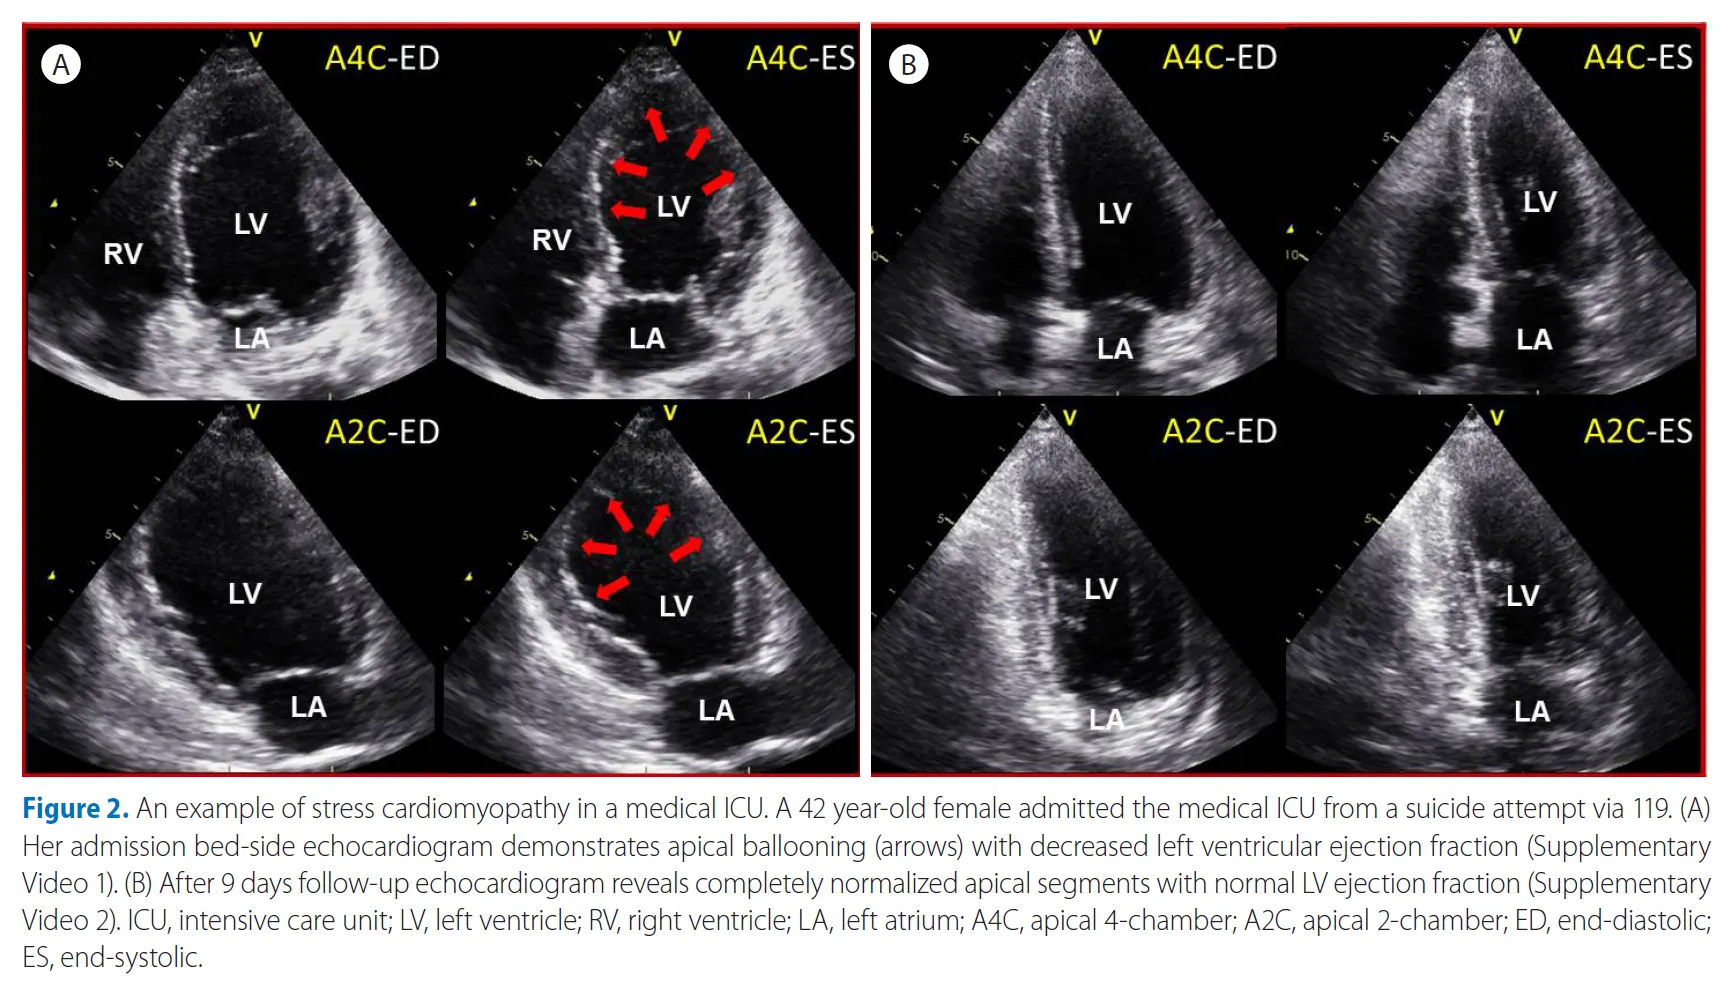

좌심실 심첨부에 국한된 벽운동 장애(apical ballooning)는 SCIMP 의심

식도 정맥류 출혈로 인한 다량의 출혈과 쇼크로 중환자실에 입원한 56세 여성의 침대 옆 심초음파 검사 예시입니다.

식도 정맥류 출혈로 인해. (A) APLX view는 전방 승모판 전단(화살표)의 수축기 전방 운동을 보여줍니다. (B) 좌심실 유출로의 CW 도플러 추적은 Late peaking signal, 즉 최고 압력 구배 61 mmHg로, 배경의 초기 및 고속 승모판 역류 신호와 구별됩니다. (C) AP4C view는 super-normal LV systolic function 을 보여주지만, RV는 작다. (D) 하대정맥의 늑골 하보기 (빈 화살표)는 전체 호흡기 동안 거의 붕괴 된 것을 보여줍니다. 거의 collape된 IVC와 작은 RV는 이 저혈량성 쇼크에서 매우 낮은 체적 상태를 나타냅니다.